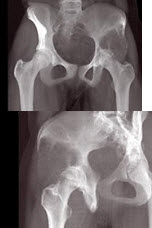

282、单项选择题

女,31岁,左侧髋部疼痛1月余,有压痛,压之有捏乒乓球感,结合影像学检查,最可能的诊断是()

A.骨囊肿

B.骨巨细胞瘤

C.动脉瘤样骨囊肿

D.成软骨细胞瘤

E.骨结核

点击查看答案